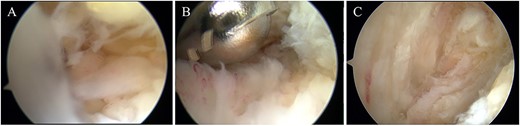

The surgery was performed under general anesthesia in the prone position using an air tourniquet. Based on the report by van Dijk et al. [11], the posteromedial and posterolateral portals were created. The posterolateral portal was used as a viewing portal, the posteromedial portal as a working portal. First, the anterior aspect of the Achilles tendon was observed using a 4.0-mm-diameter 30° arthroscope. There was hyperemic synovium located between the Achilles tendon and the posterosuperior calcaneal prominence and in which was removed with a 3.5-mm-diameter motorized shaver. After confirming no impingement sign between the Achilles tendon and the posterosuperior calcaneal prominence, the wound was sutured, and so the surgery was concluded (Fig. 4).

(A) Hyperemic synovium was located between the Achilles tendon and the posterosuperior calcaneal prominence and (B) removed with a 3.5-mm-diameter motorized shaver. (C) After confirming no impingement sign between the Achilles tendon and the posterosuperior calcaneal prominence, the surgery was concluded.